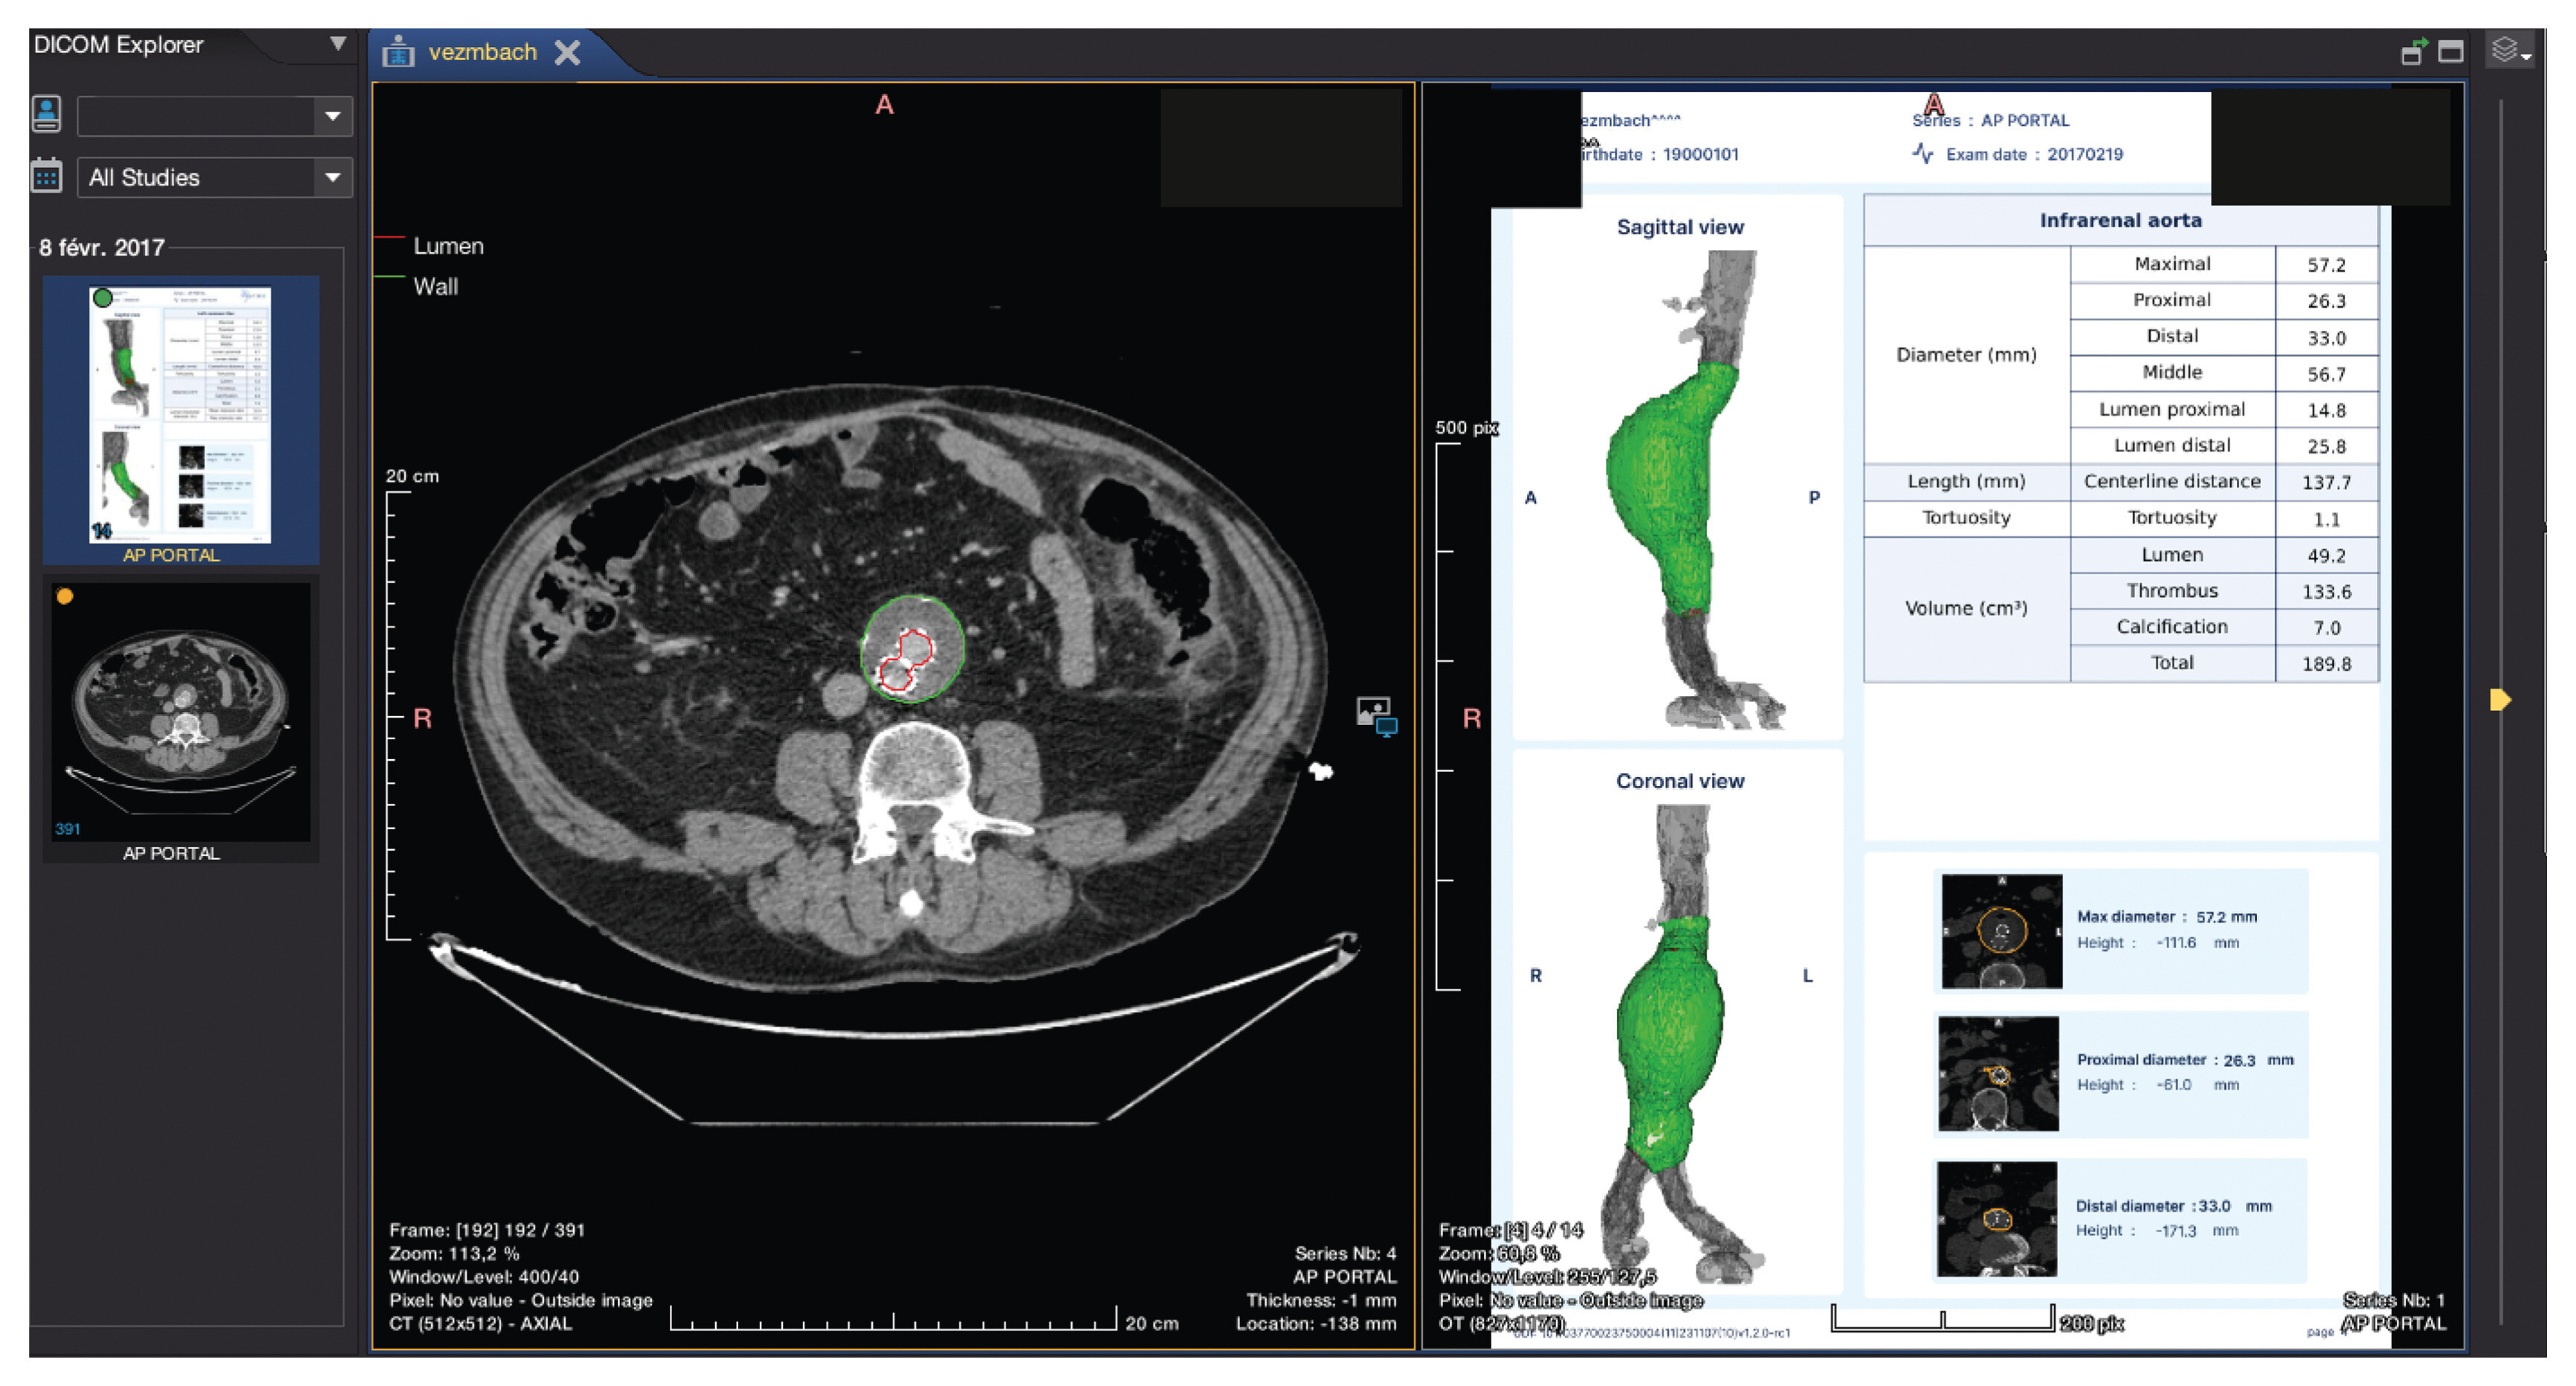

Visualisation du sac anévrismal à l'aide de la méthode entièrement automatisée établie sur l'intelligence artificielle. (A) Reconstruction 3D d'un sac anévrismal, mettant en évidence la lumière en rouge et le thrombus en vert. (B) Images de numérisation traitées.

Rapport complet sur l’anévrisme du patient utilisant le logiciel basé sur l’intelligence artificielle.